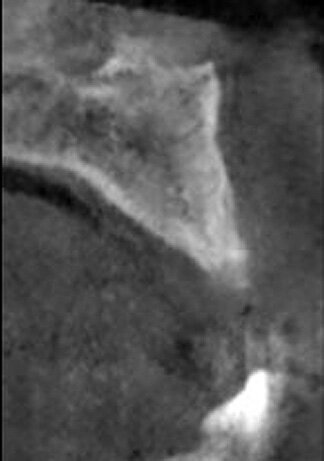

A 52-year-old male patient presented missing the left central and lateral maxillary incisors with a desire to have implants to replace the missing teeth and a fixed prosthetic approach. The patient indicated that the teeth had been extracted eight years before, and clinical examination noted a deficient facial aspect of the ridge at the extraction sites and healthy soft tissue (Fig. 1). A cone-beam CT (CBCT) was taken and evaluated. Cross-sectional views of the edentulous space confirmed inadequate width of the ridge in the facial-palatal dimension to house implants at the adjacent sites (Fig. 2). The patient was informed of the clinical findings and a discussion on augmenting the site with an osseous graft would be necessary for implant placement. As insufficient bone would not permit simultaneous implant placement at the time of grafting, the patient was informed that a healing period of four to six months would be needed between graft placement before implants could be placed. This would then be followed by a four- to six-month period to allow the implants to osseointegrate before any restoration could be placed on the implants. The patient agreed to treatment and was appointed.

Fig. 2: CBCT cross-section demonstrating insufficient ridge width facial-palatally to permit implant placement in the healed extraction sites.